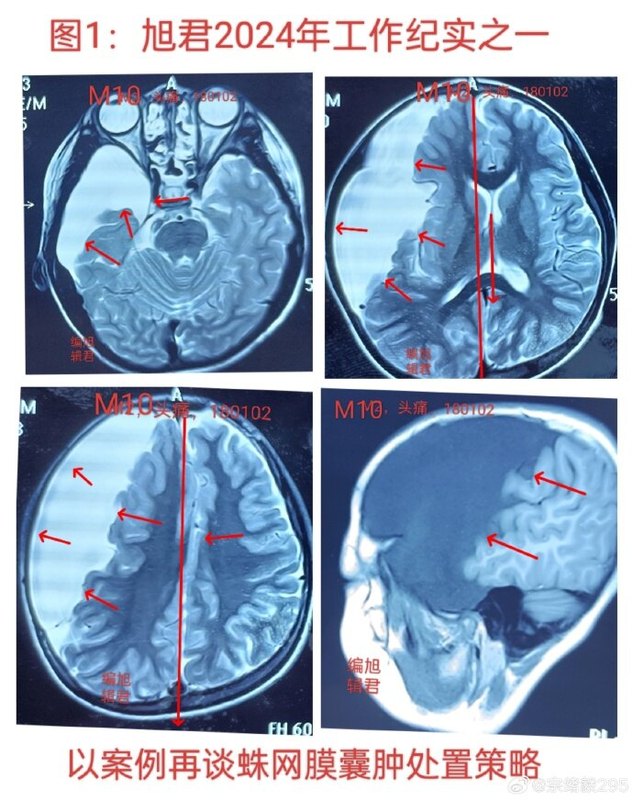

近來接診一位16歲患者。在10歲時(shí)曾因枕部頭痛接受了CT/MRI檢查,發(fā)現(xiàn)右額顳頂區(qū)域存在一個(gè)巨大的蛛網(wǎng)膜囊腫,見下【圖1-2】。在某醫(yī)院接受了手術(shù),部分囊壁和囊腫被切除,并進(jìn)行了腦池溝通術(shù)。然而,術(shù)后三個(gè)月進(jìn)行復(fù)查時(shí),見下【圖-3】,他又開始感到頭痛,尤其是左枕部位,MRI檢查顯示蛛網(wǎng)膜囊腫的情況與術(shù)前相似,見下【圖4-5】。根據(jù)MRI/CT片的觀察,術(shù)后六年囊腫似乎并沒有明顯縮小。那么,造成這種情況的原因是什么呢?這個(gè)病例的特點(diǎn)如下:1、患者在10歲時(shí)出現(xiàn)了頭痛,主要集中在枕部。2、存在一個(gè)巨大的蛛網(wǎng)膜囊腫,導(dǎo)致顱骨略微外突,腦中線發(fā)生偏移。3、囊腫位于腦組織側(cè),腦溝的起伏清晰可見。從這些特點(diǎn)可以看出,患者患有先天性腦發(fā)育不全,近十年來,腦組織一直受到囊腫的壓迫和移位,可能導(dǎo)致腦組織的順應(yīng)性減弱,即腦組織的彈性受損。因此,即使手術(shù)將囊腫與腦池相連,腦組織很難恢復(fù)正常狀態(tài),術(shù)后效果通常也不理想,就像這個(gè)病例一樣。因此建議,當(dāng)被診斷為蛛網(wǎng)膜囊腫時(shí),一定要尋求多位醫(yī)師的意見,聽取他們的建議,進(jìn)行冷靜的綜合評(píng)估,權(quán)衡積極干預(yù)與適當(dāng)保守觀察的利弊。